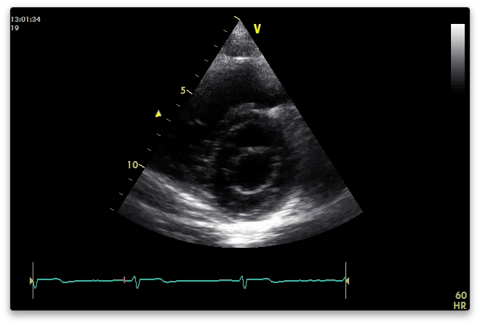

Aortic level

2D

Inspect:

- AV - should be tricuspid. Right, non and left coronary cusps as above (Royal National Lifeboat). Thickness, mobility and calcification.

- TV

- Inter-atrial septum (IAS)

- Look for thrombus in RVOT and PA if PE suspected.

- Proximal RVOT diameter immediately above the AV (should have already measured this in PLAX).

- PV annulus and main PA